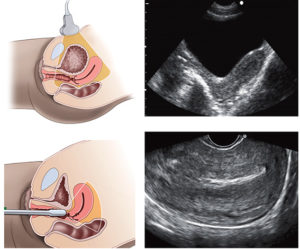

Методики диагностики

- Вагинальное УЗИ малого таза.Вагинальное УЗИ — основной метод эхографической диагностики в акушерской и гинекологической практике. Медицинский термин «УЗИ вагинальным датчиком» означает то, что оно проводится через влагалище. Женщине нужно будет либо лечь на спину, либо на бок, ноги должны быть согнуты в коленях и направлены к груди.Ультразвуковой датчик с надетым на него презервативом мягко вводится во влагалище. Перемещая наконечник датчика в разных направлениях, врач передает изображения тазовых органов на монитор. Информация, передаваемая вагинальным датчиком, отображается на экране УЗИ-аппарата в разных проекциях, а масштабирование позволяет приблизить картинку и рассмотреть интересующие детали более подробно.

Также в ходе исследования специалист периодически делает фото и записи видео результата сканирования органов малого таза, что позволит позже лучше проанализировать полученные данные и/или записать их на диск или флэш-карту. Следует иметь ввиду, что вагинальное УЗИ проводится только женщинам, начавшим жить половой жизнью. Девственницам исследование малого таза таким способом не проводят.

Поэтому придя в клинику для получения данной услуги будучи девственной, разумно будет заранее предупредить врача диагноста об этом обстоятельстве.

- Абдоминальное УЗИ малого таза. Эта методика является способом выявления патологий у детей, девочек-подростков и пациенток, не живших половой жизнью. Также применяют в акушерской практике при скринингах беременности и динамического наблюдения. Делают УЗИ абдоминальным доступом девственницам и остальным пациенткам после обязательного предварительного наполнения мочевого пузыря.

- Ректальное УЗИ малого таза. Назначается мужчинам, девушкам-девственницам и женщинам, у которых есть противопоказания к вагинальному исследованию. В первую очередь, ректальная методика диагностики органов малого таза применяется для пациенток, не живущих половой жизнью. Девственная плева делает невозможным введение датчика во влагалище без ее повреждения, поэтому используется УЗИ через задний проход. Для этого пациентка укладывается на кушетку в положении лежа на боку и подтягивает колени к животу. На датчик диаметром не более 1,5 — 2,0 см. надевают презерватив, смазывают специальным гелем и через анус вводят в прямую кишку, после чего изображение выводится на экран сканера.